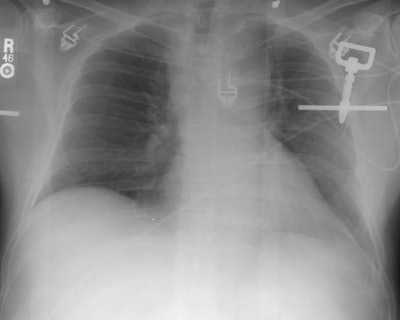

The patient was a middle aged female who had a slowly enlarging mass in the right lower lung. The patient was reluctant to have surgery, but contrast enhanced CT revealed nodule enhancement greater than 20 HU which suggested a malignant lesion and the patient agreed to surgery. The lesion proved to be a carcinoid tumor with atypical features at histologic analysis. Peripheral carcinoids are more frequently atypical as in this case.CXR revealed a right lower lobe non-calcified mass (yellow arrow):